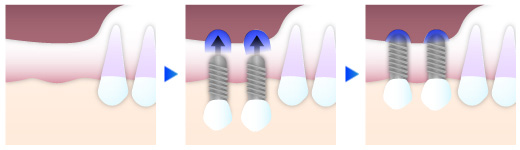

ソケットリフト

上顎のインプラント治療の際、骨の厚みが5㎜以上ある場合に行う骨造成法です。インプラントを埋入する穴に骨充填を挿入し、骨量を増やします。

サイナスリフト

上顎のインプラント治療の際、骨の厚みが5㎜以下の場合に行う骨造成法です。歯茎を切開して、上顎洞を押し上げた場所に骨充填材を設置し、骨の再生を促します。